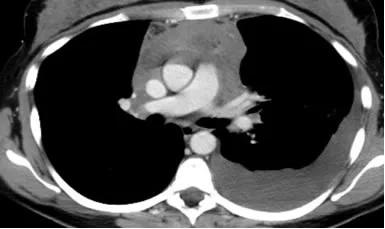

CT检查发现“肺积水”并不罕见,但胸腔内少量积液是否正常?这个问题困扰着许多患者。肺积水,医学上称为“肋膜积水”,是指液体积聚在肺脏外面的胸膜腔内。根据积液的多少和持续时间,可分为少量、中等量和大量肺积水。

少量胸腔积液在某些情况下是正常的生理现象。正常人胸腔内会有少量液体(约5-15毫升),起到润滑作用,帮助肺部在呼吸时顺畅移动。然而,当积液量超过正常范围时,就需要进一步检查原因了。

肺积水的病因复杂多样,可分为心源性和非心源性两大类。心源性肺水肿通常由心脏压力增加引起,常见于心力衰竭患者。非心源性肺水肿则可能由多种因素引起,包括肺部感染、药物反应、高海拔环境等。